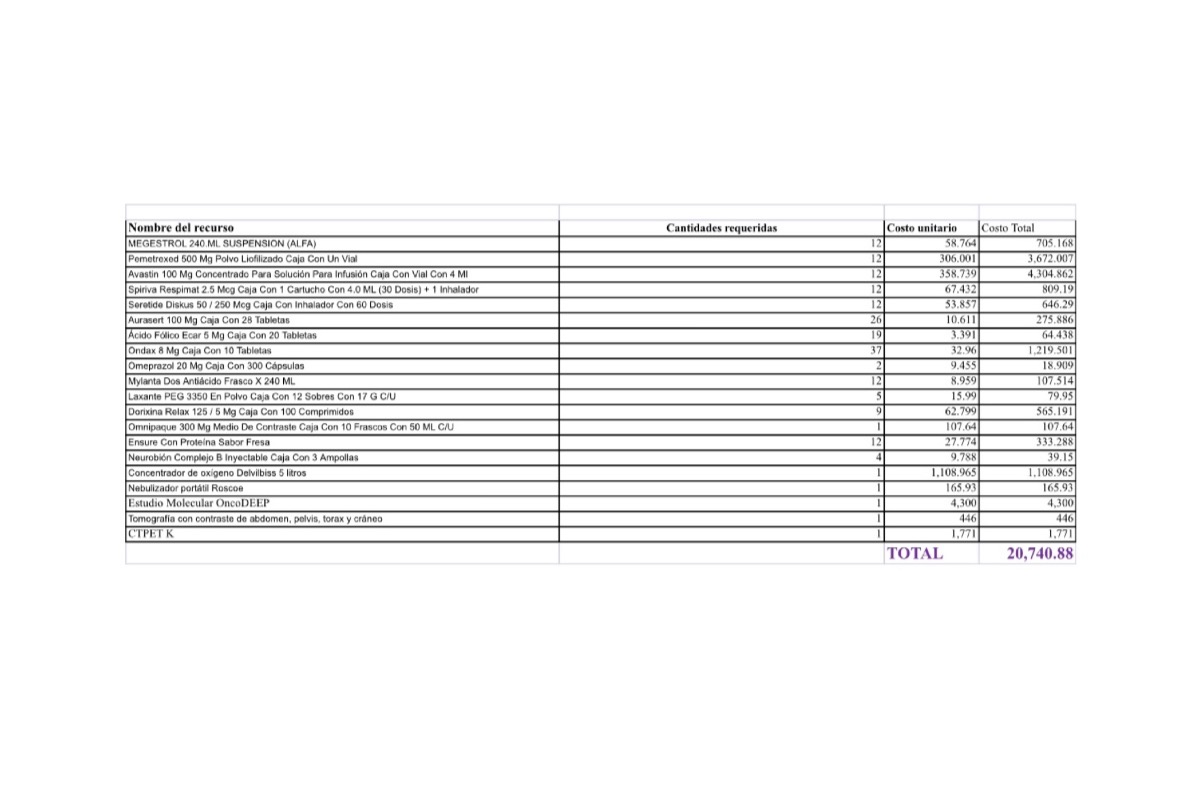

Sin embargo, aún necesita varios ciclos de quimioterapia adicionales, un examen llamado PET Scan para verificar que no tiene alguna otra célula cancerígena en su cuerpo, una operación para extraer el resto del tumor, y tratamiento para acompañar todo el proceso que podría salvar su vida.

El dinero que pedimos es para costear los ciclos restantes de quimioterapia, el PET Scan, los medicamentos que acompañan todo el tratamiento y algunos gastos de movilización, debido a que me he visto en la necesidad de hacer una pausa en mi profesión y dedicarme a atender a mi mamá, trasladarla a sus tratamientos, quimioterapias, consultas, cocinarle, darle sus medicinas y acompañarla en las noches de dolor.

A continuación les dejo el diagnóstico, los exámenes, y los presupuestos de los próximos exámenes que hay que hacerle a mi mamá.

However, she still needs several additional cycles of chemotherapy, a test called a PET Scan to verify that she doesn't have any other cancer cells in her body, an operation to remove the rest of the tumor, and treatment to accompany the entire process that could save her life. .

The money that we ask for is to pay for the remaining cycles of chemotherapy, the PET Scan, the medications that accompany the entire treatment and some mobilization expenses, due to the fact that I have seen the need to make a pause in my profession and dedicate myself to take care of my mother, to take her to her treatments, chemotherapies, consultations, cook her, give her medicines and accompany her on nights of pain.

Down here I leave the diagnosis, exams, and budgets for the next exams to be done to my mom.

Sin embargo, aún necesita varios ciclos de quimioterapia adicionales, un examen llamado PET Scan para verificar que no tiene alguna otra célula cancerígena en su cuerpo, una operación para extraer el resto del tumor, y tratamiento para acompañar todo el proceso que podría salvar su vida.

El dinero que pedimos es para costear los ciclos restantes de quimioterapia, el PET Scan, los medicamentos que acompañan todo el tratamiento y algunos gastos de movilización, debido a que me he visto en la necesidad de hacer una pausa en mi profesión y dedicarme a atender a mi mamá, trasladarla a sus tratamientos, quimioterapias, consultas, cocinarle, darle sus medicinas y acompañarla en las noches de dolor.

A continuación les dejo el diagnóstico, los exámenes, y los presupuestos de los próximos exámenes que hay que hacerle a mi mamá.

However, she still needs several additional cycles of chemotherapy, a test called a PET Scan to verify that she doesn't have any other cancer cells in her body, an operation to remove the rest of the tumor, and treatment to accompany the entire process that could save her life. .

The money that we ask for is to pay for the remaining cycles of chemotherapy, the PET Scan, the medications that accompany the entire treatment and some mobilization expenses, due to the fact that I have seen the need to make a pause in my profession and dedicate myself to take care of my mother, to take her to her treatments, chemotherapies, consultations, cook her, give her medicines and accompany her on nights of pain.

Down here I leave the diagnosis, exams, and budgets for the next exams to be done to my mom.